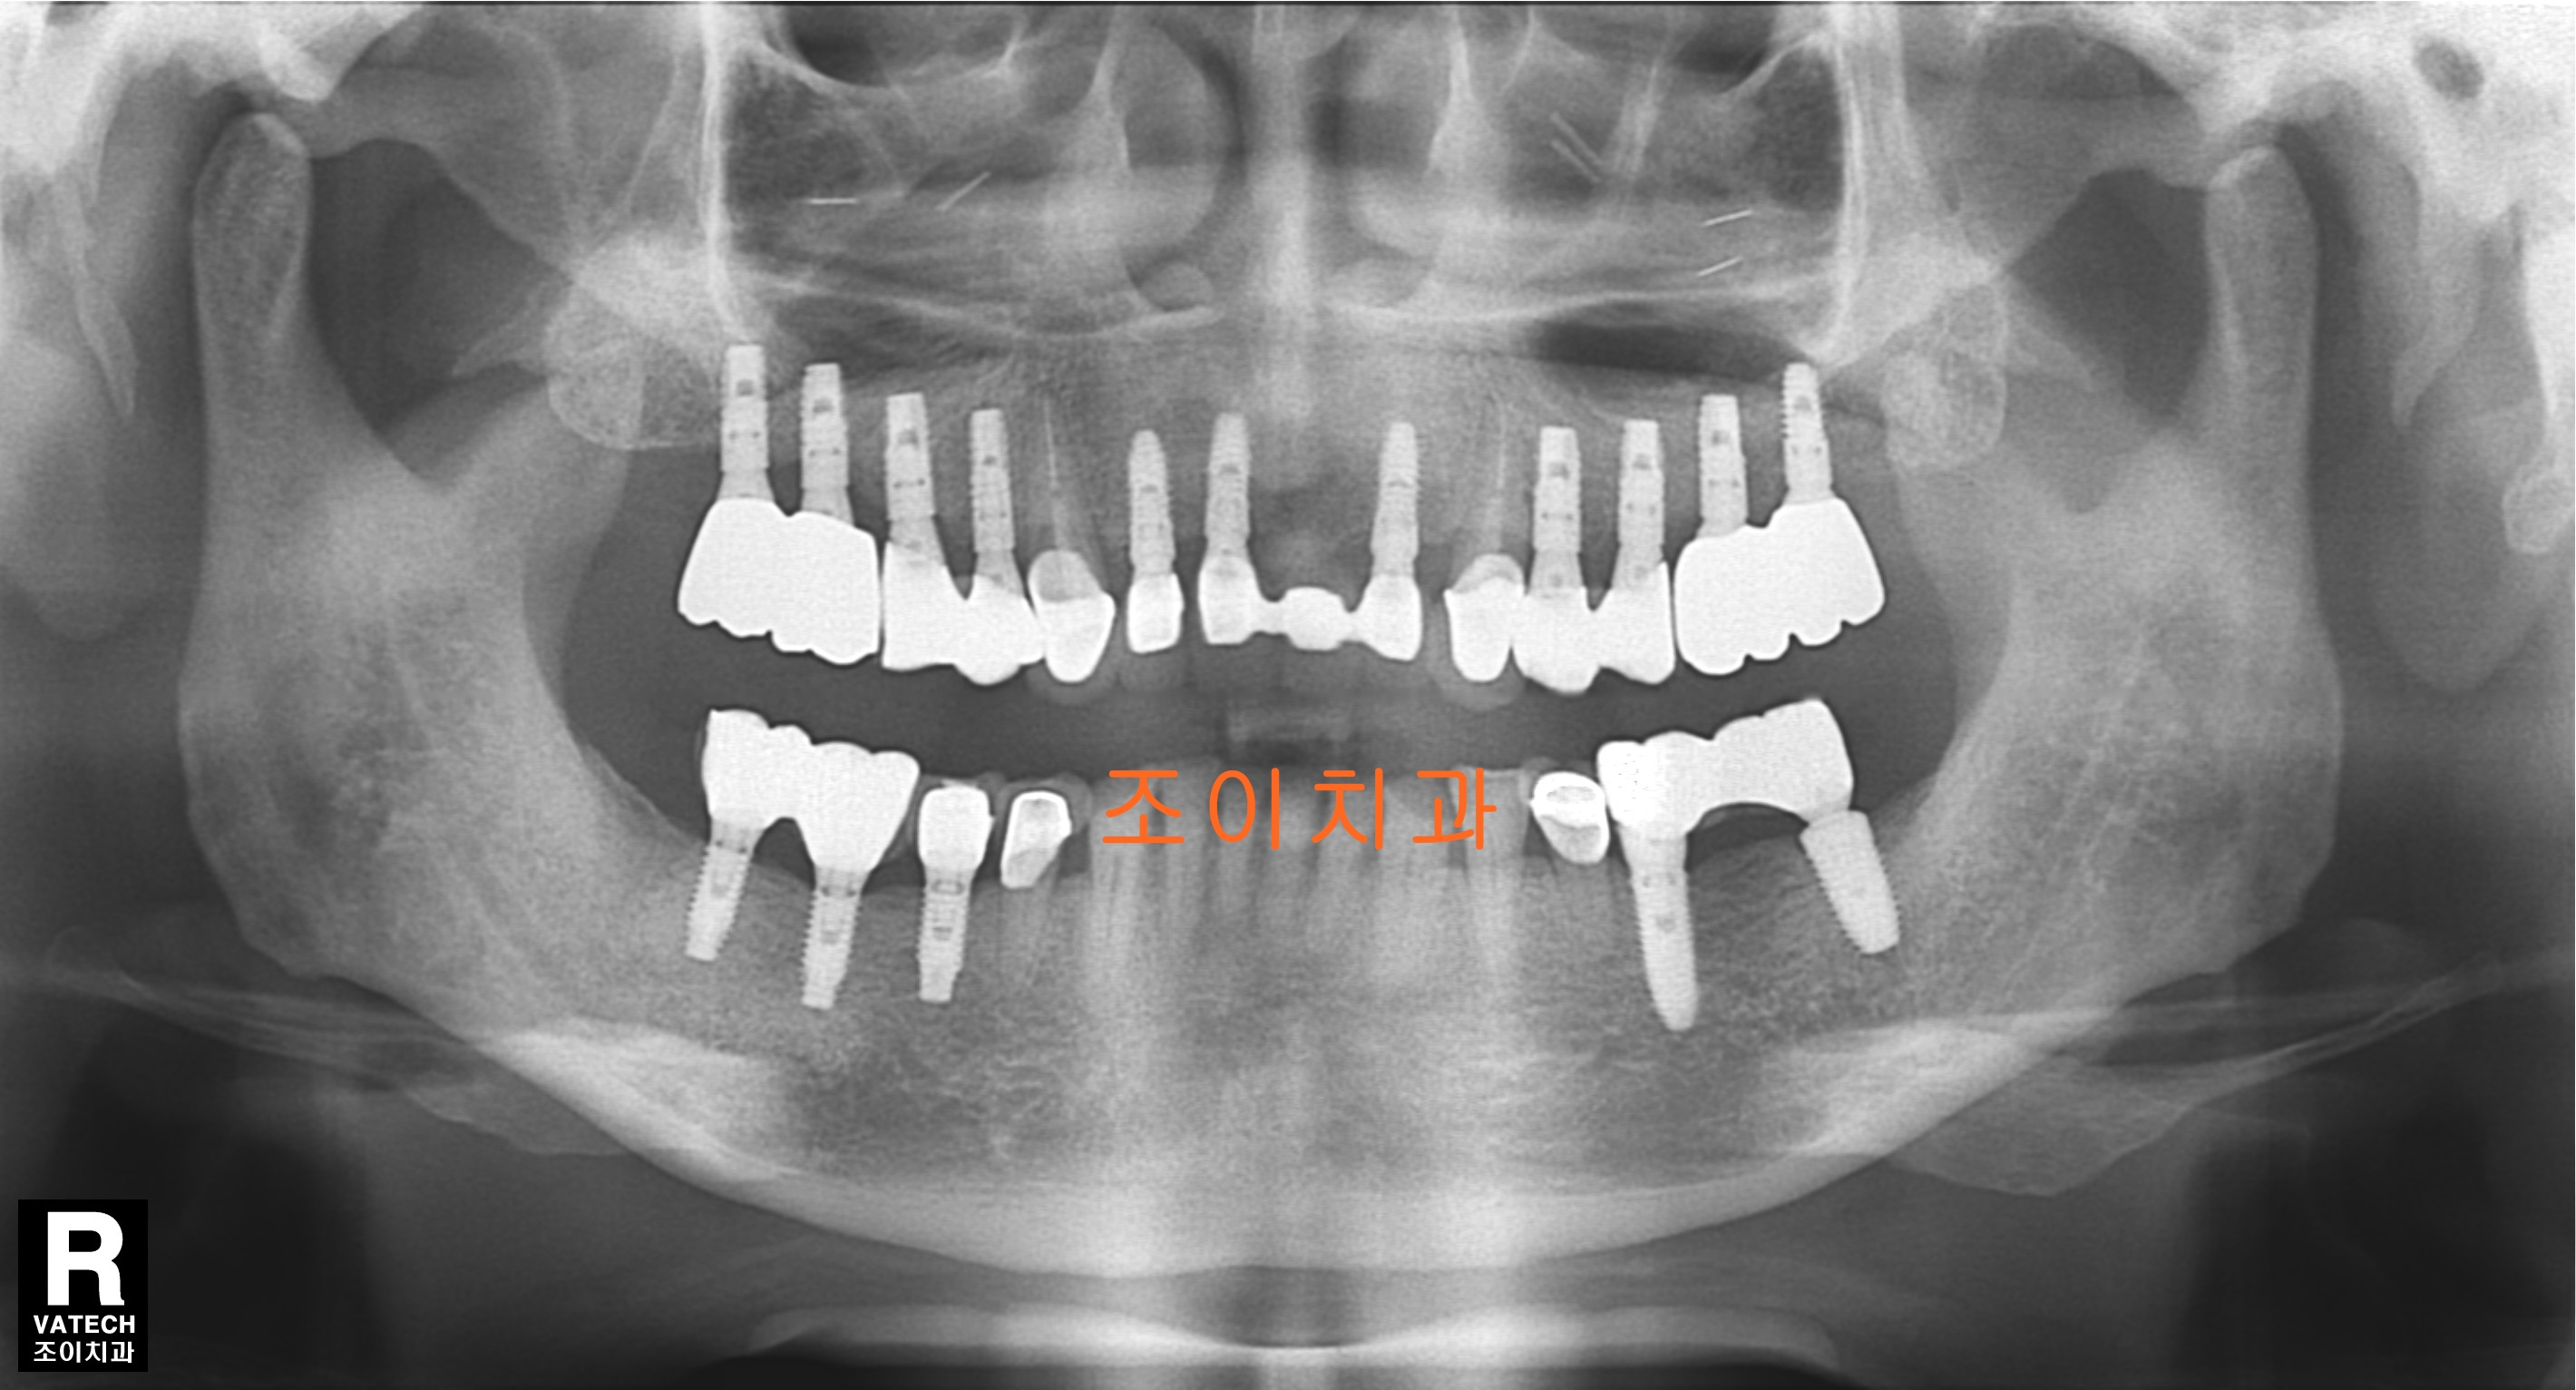

[임플란트] 제목 : 상악 전악 및 하악 구치부

틀니를 벗고 임플란트로